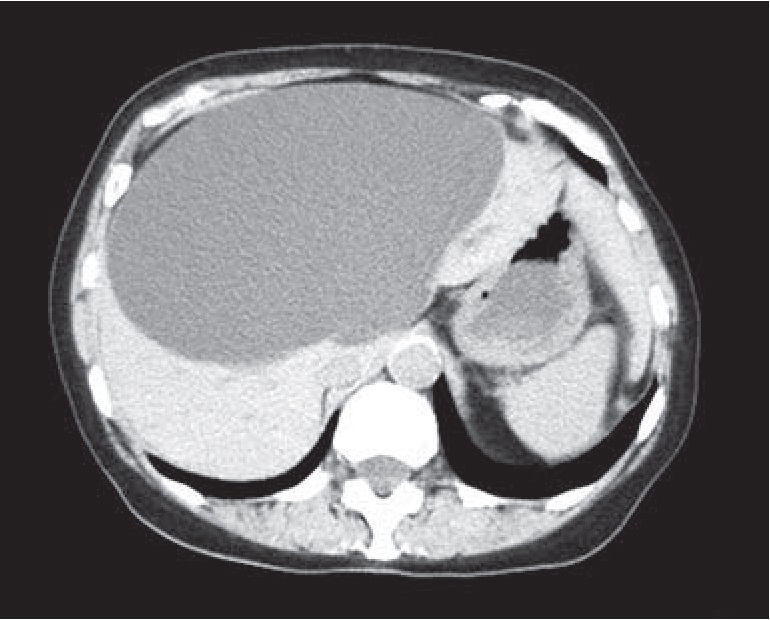

Результаты и их обсуждение. Из анамнеза известно, что 5 лет назад, во время прохождения профилактического медицинского осмотра при помощи ультразвукового исследования (УЗИ) органов брюшной полости была выявлена киста правой доли печени. В ноябре 2017 г. пациентка отметила появление болевого синдрома и дискомфорта в верхних отделах живота, которые купировались приемом спазмолитиков (но-шпа). С конца июля 2018 г. боли нарастали, в связи с чем 08.09.2018 г. пациентке была выполнена спиральная компьютерная томография (СКТ) органов брюшной полости, по результатам которой в правой доле печени обнаружено образование размерами 126×177×184 мм с однородной жидкостной структурой и четкой капсулой, а также множественные конкременты желчного пузыря с максимальным размером до 16 мм в диаметре (рис. 1). Амбулаторно был выполнен иммуноферментный анализ (ИФА) антител класса IgG к эхинококку – результат отрицательный. Пациентка обратилась в клинику факультетской хирургии им. И.И. Грекова. Была проконсультирована сотрудниками клиники, ей рекомендовали госпитализацию и оперативное лечение.

Рис. 1. КТ-картина гигантской кисты печени

С учетом лабораторно-инструментальных данных было принято решение о выполнении симультанного эндовидеохирургического оперативного вмешательства в объёме фенестрации непаразитарной кисты печени с холецистэктомией. С целью уточнения локализации непосредственно перед операцией пациентке выполнено УЗИ органов брюшной полости, по результатам которого в проекции IV, V и VIII сегментов печени лоцировалась киста размерами 130×160×170 мм объёмом 1900 см³. Стенка толщиной 3 мм, содержимое однородное. Желчный пузырь не увеличен, обычной формы, смещён кистой вправо. Стенка уплотнена, утолщена. В содержимом осадок в виде сладжа, подвижные конкременты диаметром до 14 мм в количестве 5−7.